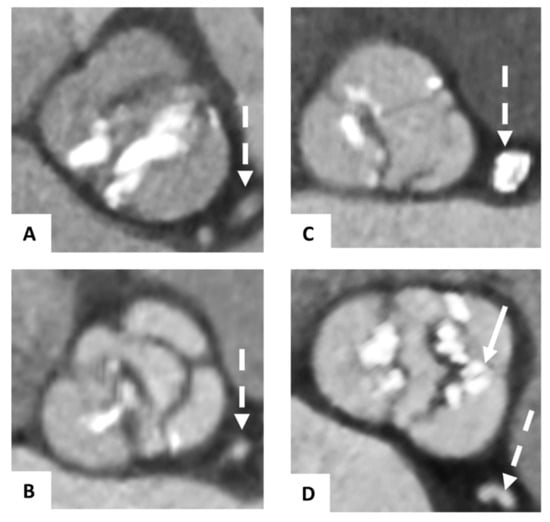

2.4. Process of Fusion Imaging

2.5. Image Analysis